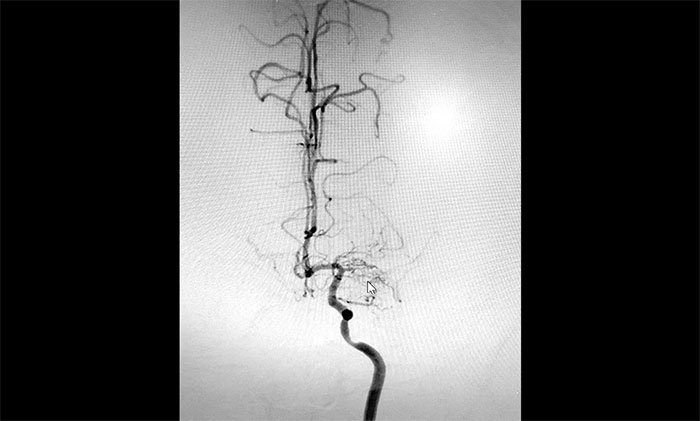

入院后,赵先生的DSA(脑血管造影)检查再次明确“烟雾病”表现:双侧大脑中动脉主干管腔纤细、分支细小;周围代偿性小血管网建立;右侧颈内动脉C3-4段纤细,显影毛糙;两侧颈内动脉C4-6段钙化形成伴管腔轻—中度狭窄。

▲DSA异常血管造影图

神经外科团队综合DSA检查结果和患者症状表现,进行了科学、审慎的评估。于耀宇主任谈到,患者双侧颈内动脉虹吸部和大脑中、前动脉主干近段明显狭窄、近乎闭塞,异常血管网形成。双侧大脑半球多发供血区灌注不足,尤以右侧缺血较为明显。